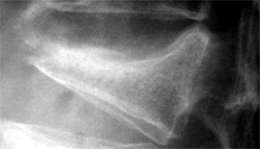

椎骨に縦方向の直達外力が加わり、その外力に耐えきれずに押し潰されて圧迫骨折が生じます。通常椎体の前方がつぶれてくさび形になります。

画像は側面から撮影したレントゲン写真です。脊椎の椎体前方がくさび形に変形しているのが分かります。